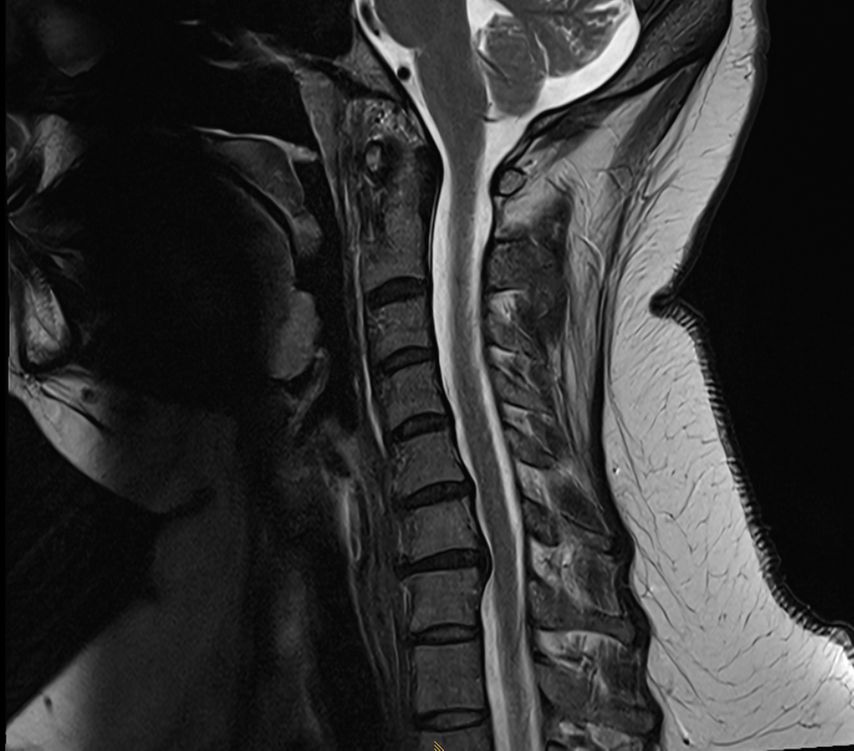

Intraoperative 3D-Visualisierung

Die Navigation stellt nicht nur beim Einbringen von Implantaten eine Hilfe dar, sondern kann auch in anatomisch herausfordernden Situationen rein zur Verbesserung der Orientierung zu Hilfe genommen werden. Mögliche Anwendungsfelder stellen hier beispielsweise die untere HWS oder der zervikothorakale Übergang dar, welche im konventionellen Röntgen teilweise schwer darstellbar sind. Abbildung 16 zeigt den MR-Befund einer 32-jährigen Patientin, die auswärtig zur ACDF C6/7 indiziert wurde, wobei der Eingriff dort aber aufgrund der Unmöglichkeit, die HWS unter Durchleuchtung entsprechend einzustellen, nicht erfolgte. Abbildung 17 zeigt das intraoperative Röntgen mit bereits kräftigem Schulterzug, in dem aber nur mehr das Segment C4/5 sicher beurteilt werden kann. In diesem Fall erfolgte mittels O-Arm der Eingriff navigiert. Ein anderes Beispiel ist die Anwendung zur Orientierung bei Osteotomien, wo die Navigation an unserer Klinik ebenfalls standardmäßig angewendet wird. Abbildung 18 zeigt einen intraoperativen Screenshot im Rahmen der Navigationsanwendung bei einer thorakalen Corporektomie (Th12) von dorsal im Rahmen einer Tumorresektion. Auch bei verkalkten Bandscheibenvorfällen, wie in Abbildung 19 dargestellt, kann die Navigation zur besseren intraoperativen Orientierung herangezogen werden. Ein weiteres Beispiel der vielfältigen Anwendungsmöglichkeiten der Navigation zeigt Abbildung 20. In diesem Fall wurde im Rahmen einer C1/2-Verschraubung nach Harms das Gelenk C1/2 beidseits navigiert zur besseren Fusion angefrischt.